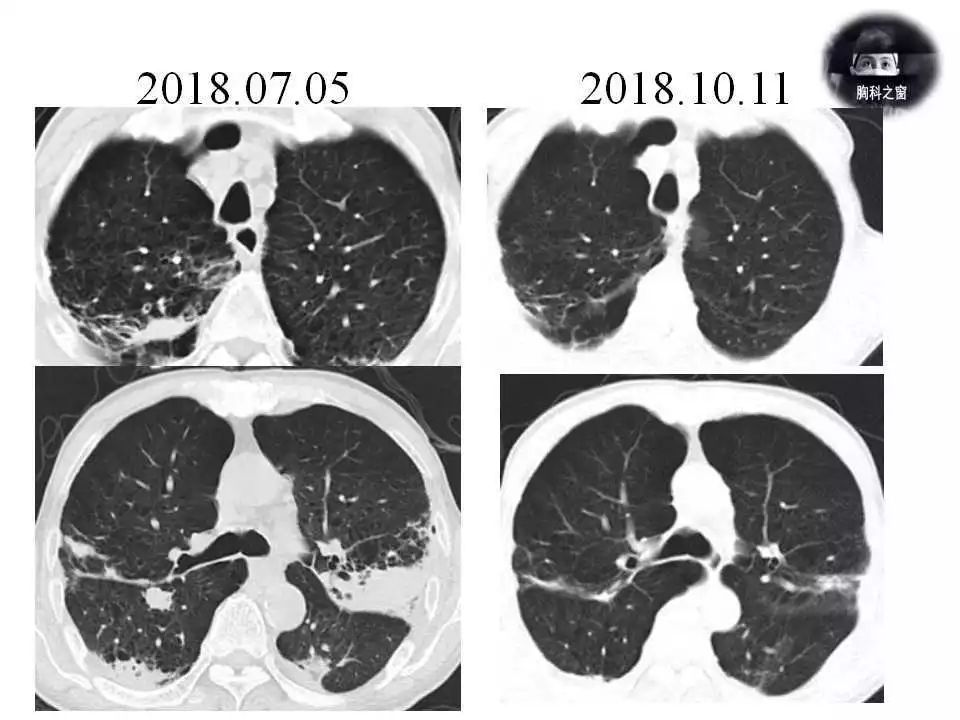

240期轮值病例结果肺奴卡菌病

图片尺寸960x720